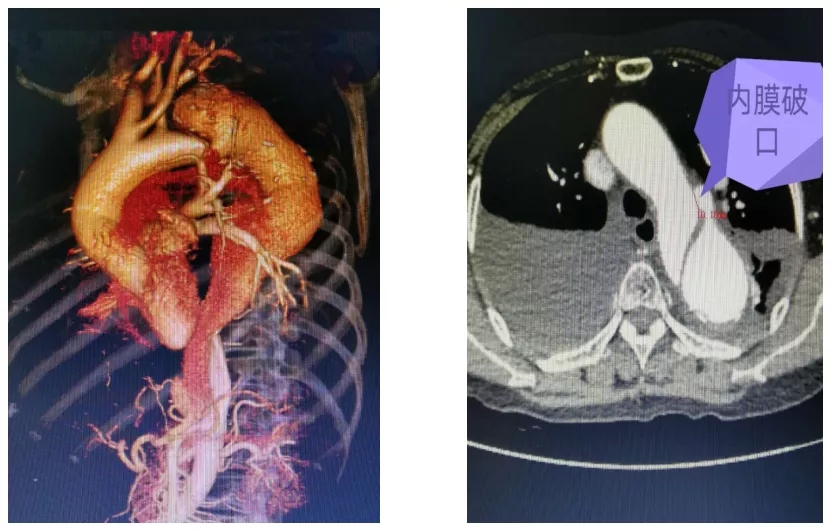

医院查主动脉CTA结果示:主动脉夹层(stanford B型),降主动脉、腹主动脉上段瘤样扩张,左房及左下肺受压,立即转院至罗湖医院血管外科,入科后予镇痛、镇静、降血压心率,完善各项检查的治疗。

术前患者CTA检查

术中见主动脉夹层(stanford B型),破口位于降主动脉起始处,破口大小1厘米,假腔压迫真腔特别明显,造成真腔狭窄。

徐阿姨的主动脉夹层是Stanford-B型,如下图